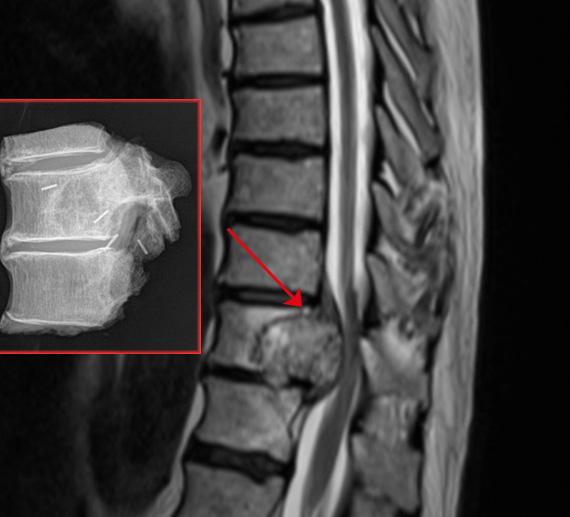

Cirujanos del Hospital Vithas Nisa 9 de Octubre han realizado una resección en bloque de un cordoma que afectaba a tres vértebras. La intervención, compleja de por sí, se realizó a través de una vía posterior única de acceso para la resección y reconstrucción de la columna.

Recientemente, el equipo que dirige el Dr. Antonio Martín Benlloch ha intervenido con éxito en el Hospital Vithas Nisa 9 de Octubre a un paciente con un cordoma en la columna torácica, que en su evolución –afectaba a una vértebra y a las inmediatamente superior e inferior- ponía en riesgo la movilidad del paciente y que, "estaba produciendo una compresión de la médula espinal", afirma el Dr. Martín.

El paciente intervenido recientemente en el Hospital Vithas Nisa 9 de Octubre se trasladó a Valencia desde otra comunidad autónoma ante la imposibilidad de ser tratado en su ciudad de origen. "La lesión había crecido hasta ocupar la práctica totalidad del espacio epidural y estaba comprometiendo la médula; afectaba de lleno a una vértebra y a las adyacentes". Pese a su complejidad, el hecho de que la lesión tumoral no hubiera evolucionado hacia la parte exterior de la columna, permitió resecar el tumor mediante una única vía de acceso.